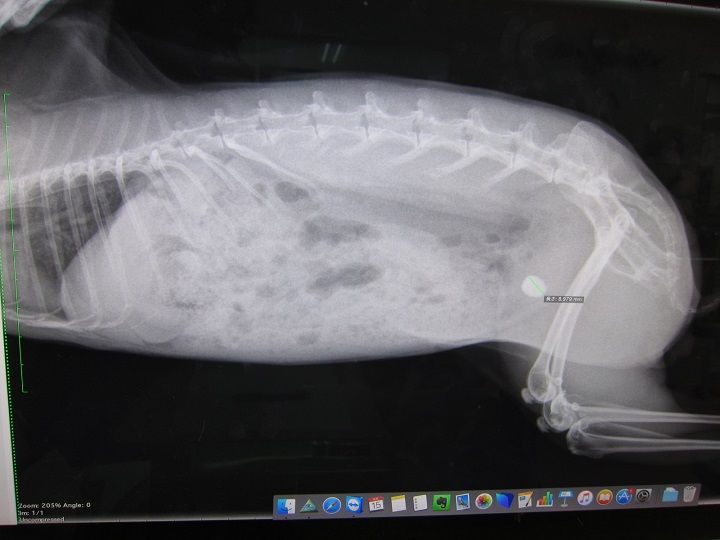

まさかあの9mmの石が出るとは…何で出たんかとかお話の前に、

まずは、石ゼロを確定させるべく早々レントゲンへ。

8.9てぇ!めちゃデカなってるし!

すんごい早くない?あまりにデカなるの早すぎひん

向かって左が今回、右がこないだ。

光の加減で膀胱全体が白っぽく見えますが石はありませんっ

石はありませんっ